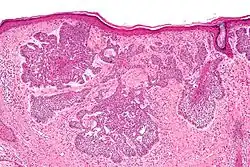

Micrograph of a basal-cell carcinoma, showing the characteristic histomorphologic features (peripheral palisading, myxoid stroma, artefactual clefting), H&E stain

Basal-cell carcinoma (BCC) is named after the basal cells that populate the lowest layer of the epidermis due to the histological appearance of the cancer cells under the microscope.[16] Nevertheless, not all BCCs originate within the basal layer.[16] Some are thought to develop from the folliculosebaceousapocrine germinative cells known as trichoblasts. Trichoblastic carcinoma is a term used to describe a rare and potentially aggressive malignancy that is also thought to arise from trichoblasts and may resemble a benign trichoblastoma (differential diagnosis can be challenging).[17][18][19] It has been suggested that lesions diagnosed as trichoblastic carcinoma may actually themselves be BCC.[20]

Nodular basal-cell carcinoma (also known as "classic basal-cell carcinoma") accounts for 50% of all BCC.[29] It most commonly occurs on the sun-exposed areas of the head and neck.[30]: 748 [31]: 646  Histopathology shows aggregates of basaloid cells with well-defined borders, showing a peripheral palisading of cells and one or more typical clefts.[29] Such clefts are caused by shrinkage of mucin during tissue fixation and staining.[32] Central necrosis with eosinophilic, granular features may also be present, as well as mucin. The heavy aggregates of mucin determine a cystic structure. Calcification may also be present, especially in long-standing lesions.[29] Mitotic activity is usually not so evident, but a high mitotic rate may be present in more aggressive lesions.[29] Adenoidal BCC can be classified as a variant of NBCC, characterized by basaloid cells with a reticulated configuration extending into the dermis.[29]